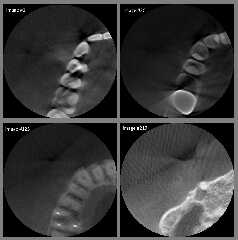

I have attached a sample of my original DICOM images (as converted to

8-bit .png) just to show what the problems are. I think that the images you are

using are of *much* higher quality.

In my opinion, my dentist needs to purchase an improved CT scanner! ;-)